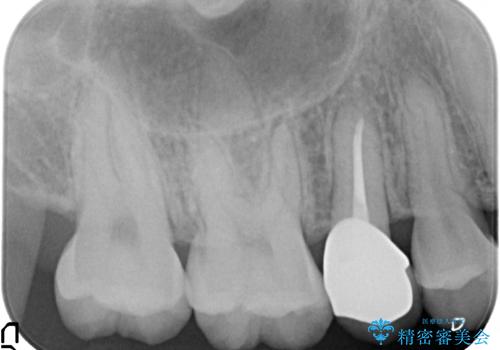

歯周外科治療で歯の高さを出し、外れにくくしました。

- 21万円(右上4:ジルコニアクラウン10万円、仮歯 1万円、歯周外科治療(APF) 10万円、矯正用仮歯 2万円費用は治療当時の料金となります

角化歯肉の幅がしっかり合ったため、歯肉をずらすAPF(アピカリ)でなく、切除療法を行いました。

骨外科の量は多かったですが、術直後見られた動揺も治っています。